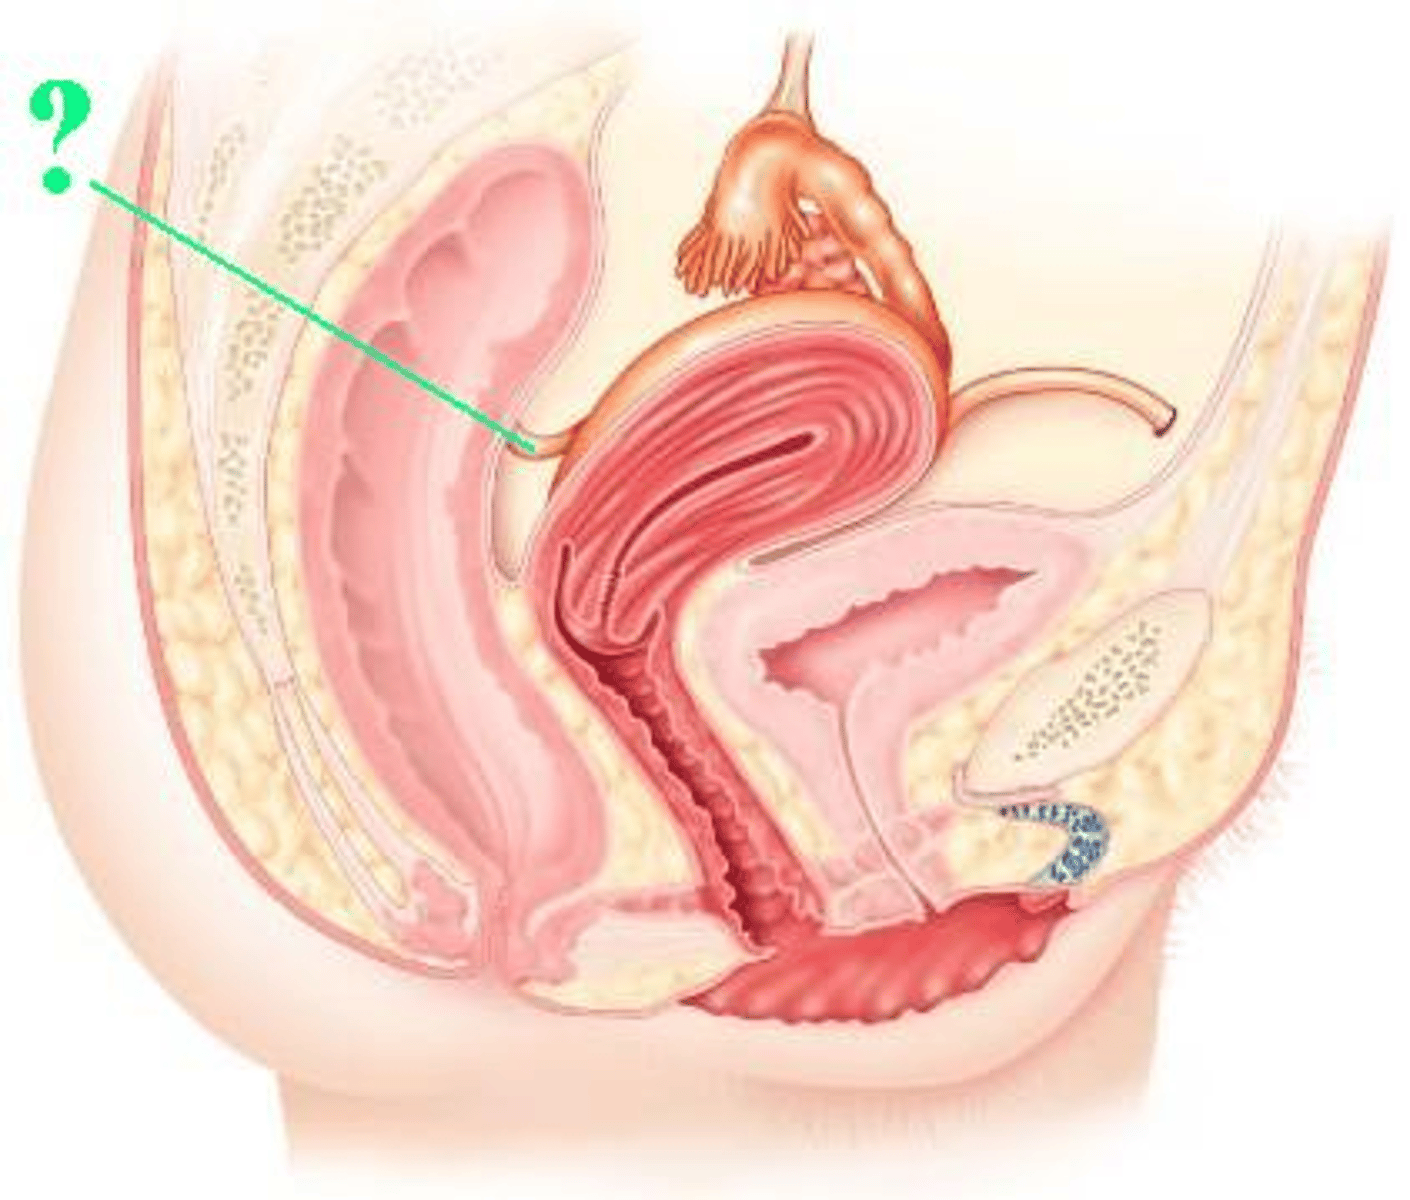

urinary bladder

Identify the indicated structure.

uterus

suspensory ligament